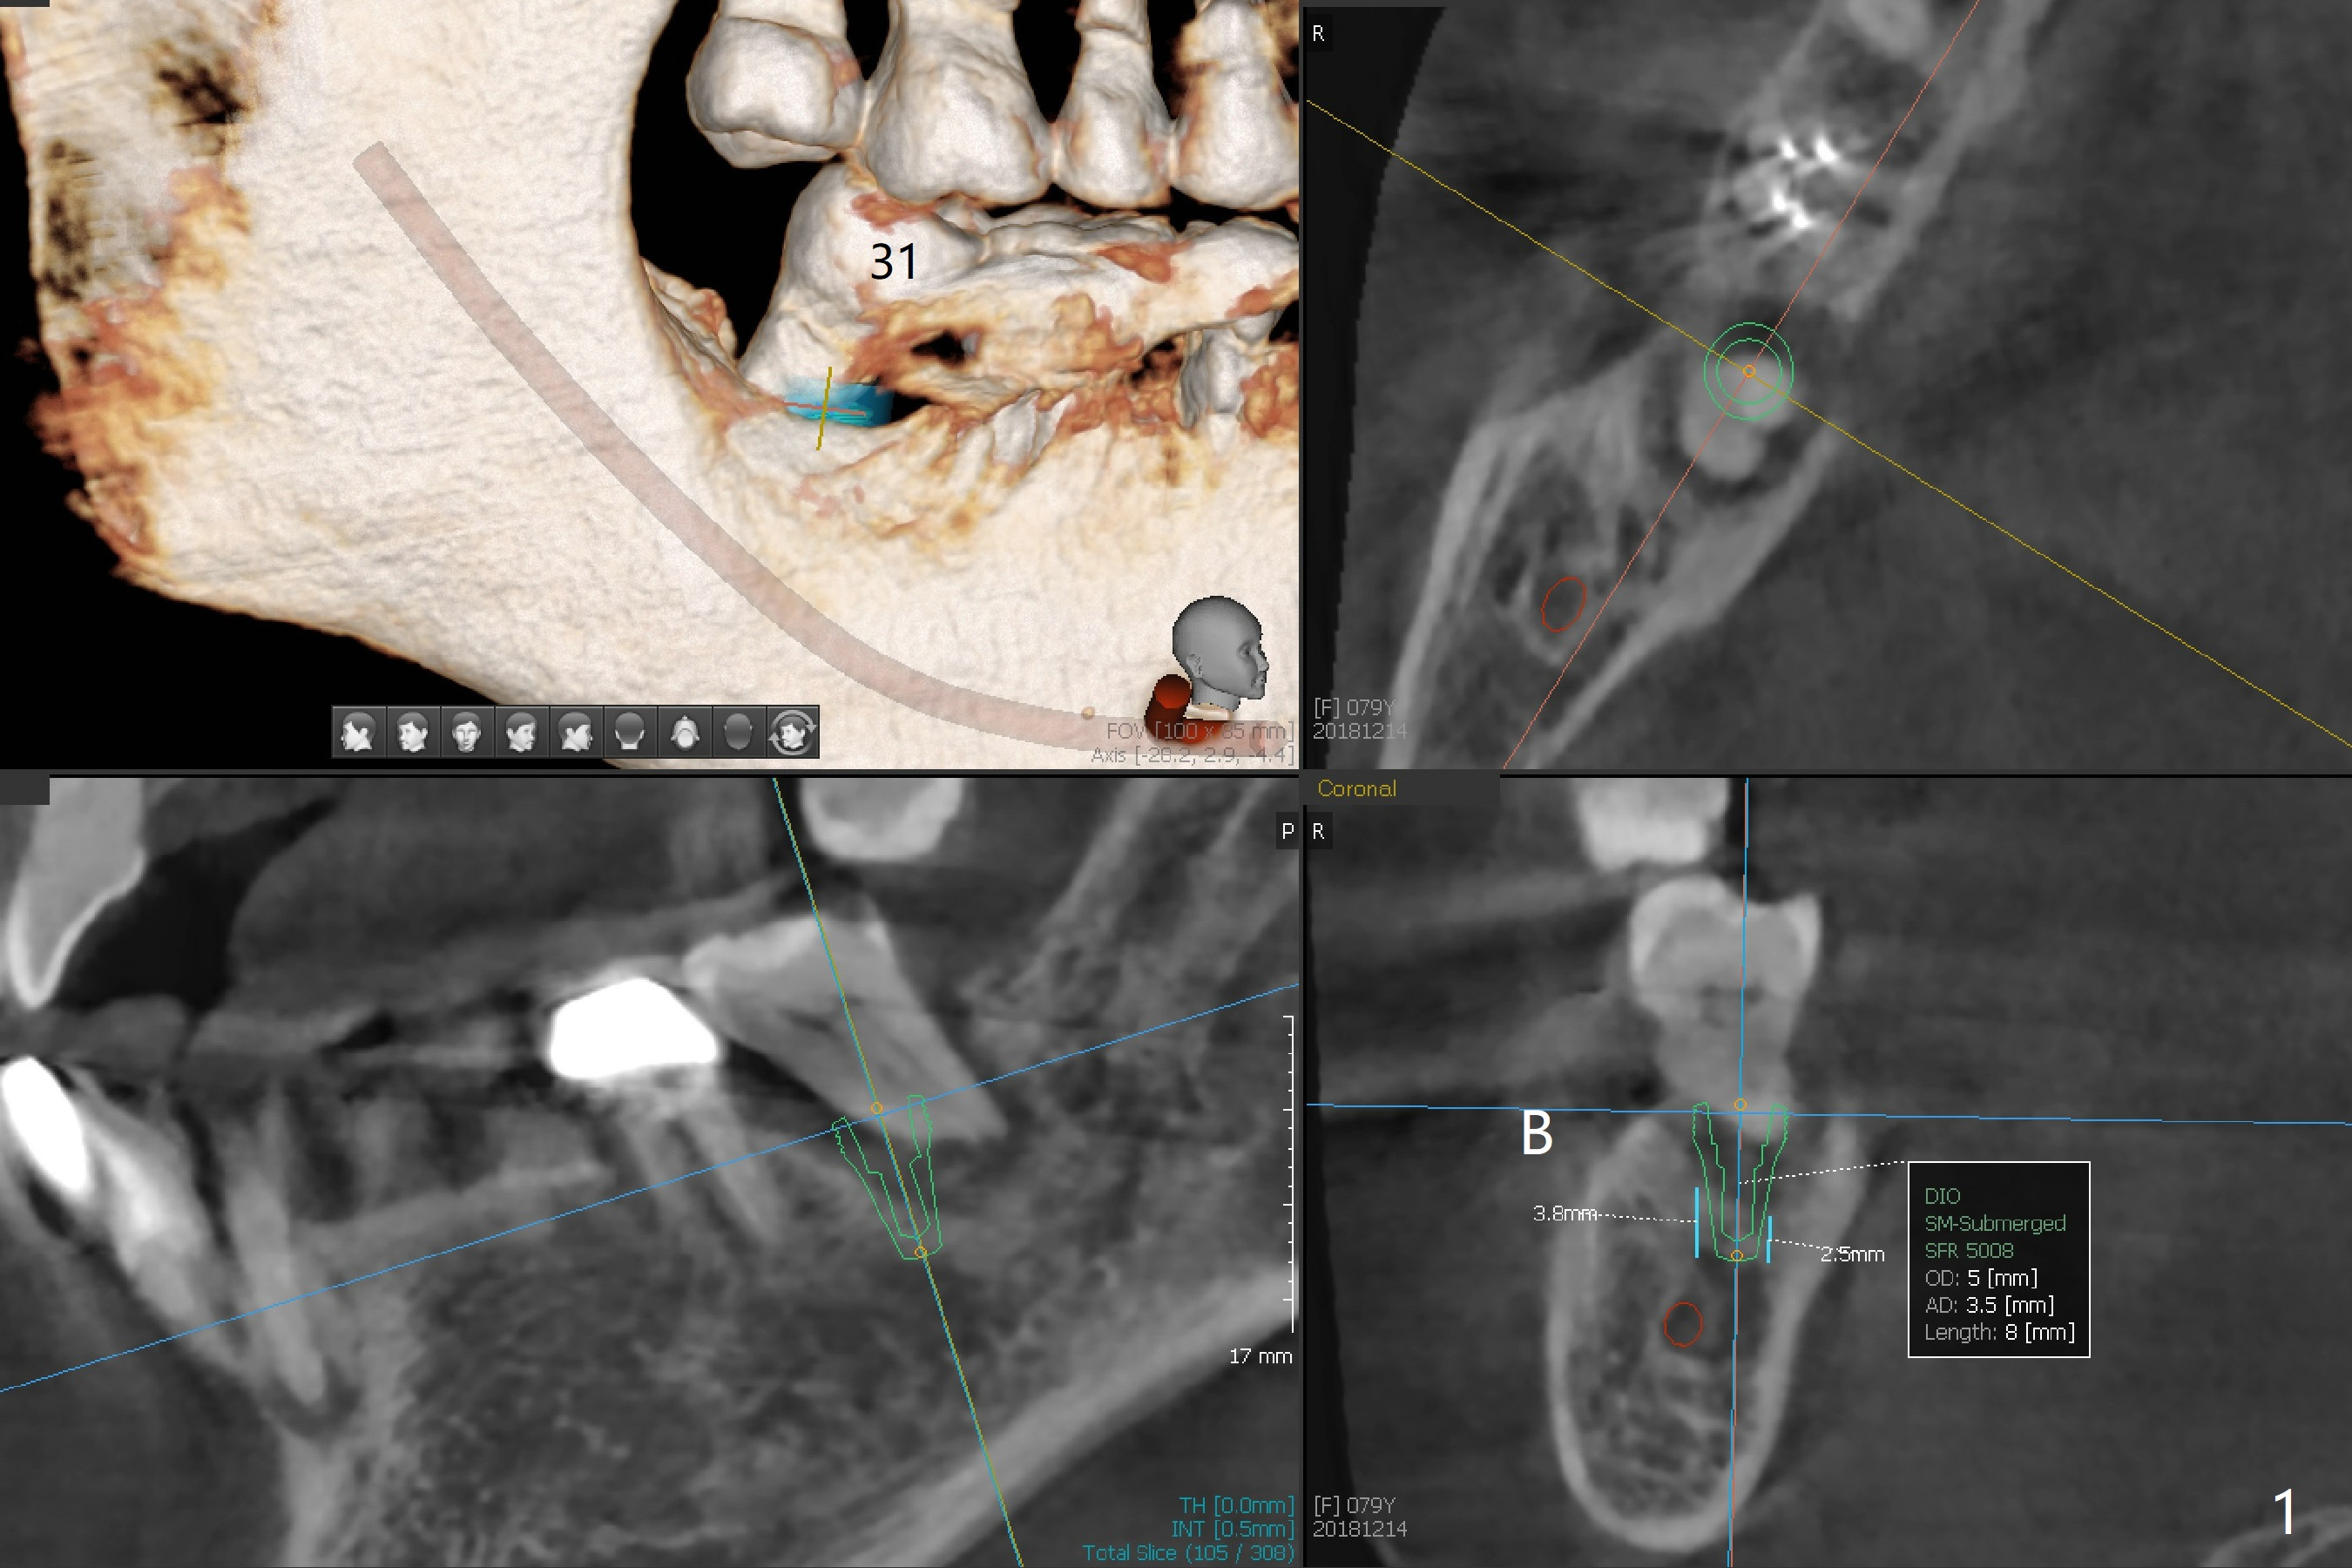

A 79-year-old woman returns to clinic suddenly, requesting extraction of the tooth #31 with mobility III (3 years 8 months post cementation for #25; 2 years 6 months post cementation for #18-20; Fig.4). An immediate implant is planned (Fig.1). After extraction, the large socket has relatively small opening, seemingly easy to keep bone graft in place. The immediate implant with 2-3 mm native bone may not have primary stability, most likely losing its ability to hold bone graft. Therefore socket preservation is conducted at #31. In contrast there is enough bone for an immediate implant at #15 (Fig.2) with palatal root fracture (Fig.3 (palatal view)).